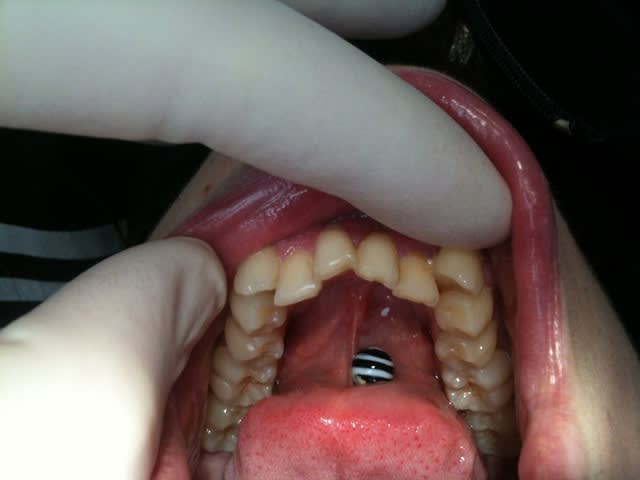

j'ai reçu ce matin une patiente (28 ans) en consult' (dsl pas de photo):

elle présentait classe 1 molaire droite et gauche

un encombrement antérieur maxillaire et mandibulaire+++ avec 13 en vestibulo-topie, des inversés d'occlusion (12/43 et 23/33)

bref le gros bordel devant

Voici les photos prise d'un iphone en speed :)

j'en conviens hygiène pas top du tout mais un seul soin en bouche et pas de carie (faudrait peut être penser à jouer à l'euromillions :)

Si la patiente est motivée pour agir je ne laisse pas tel quel, comment veux-tu que l'hygiène soit correcte dans ces conditions ? Elle a va faire une carie et une poche paro à ce niveau c'est quasiment certain.

1er cas: motiver, vérifier que les soins locaux sont faits et efficaces sinon ne rien faire et l'adresser ailleurs.

Ensuite: comment fonctionnent langue, deglutition et respiration.... il faudrait expanser pour recuperer le bas et alors il risque de se faire de la place en haut et il va alors manquer la canine....

Perso j'extraie pas, j'explique et si elle veut pas je lui dis d'aller ailleurs. 28 ans c'est tros jeune pour perdre une canine saine.